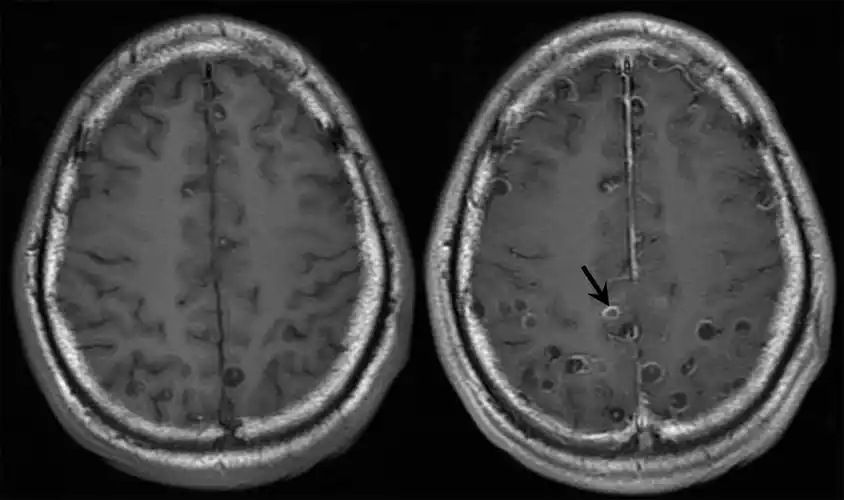

图2-8-3 多头蚴寄生在一侧脑半球【诊断】根据其特殊的症状,病史做出